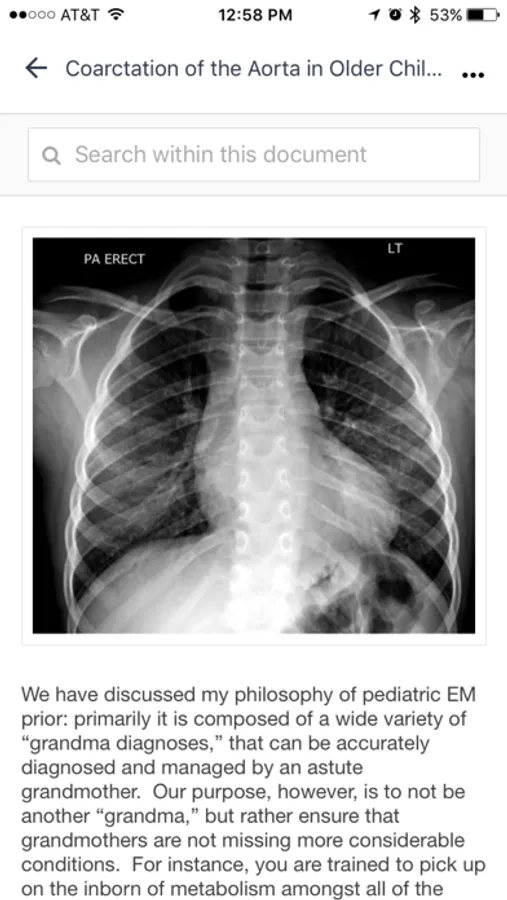

Peds EM education in bite-sized morsels. Published weekly with references included. This resource is designed to assist at the bedside. Developed by Sean M. Fox, MD, FACEP, FAAP, Associate Professor, Assistant Residency Program Director, & Emergency Medicine Residency Program at the Department of Emergency Medicine at Carolinas Medical Center.